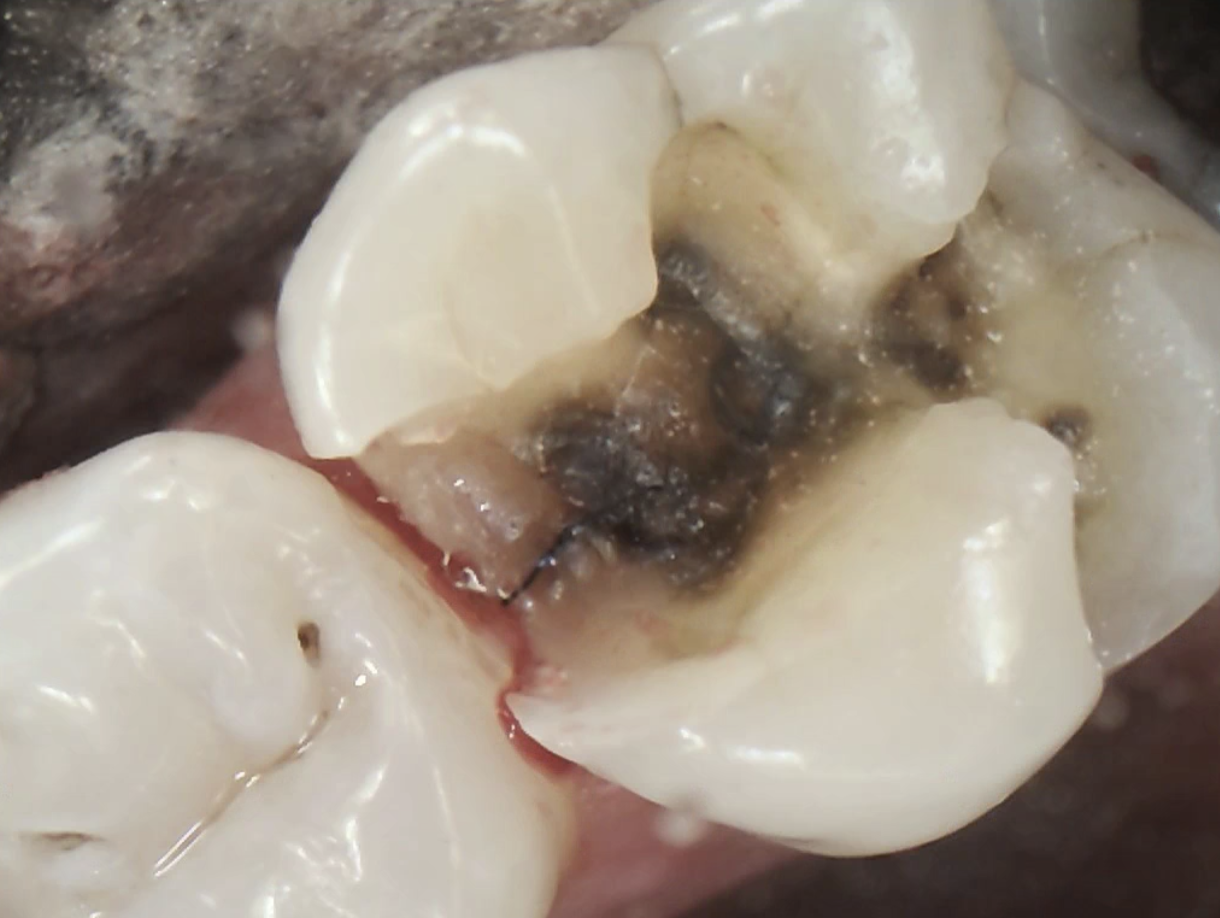

Broken Tooth with Cavity

Fractured Tooth and Broken Metal Filling